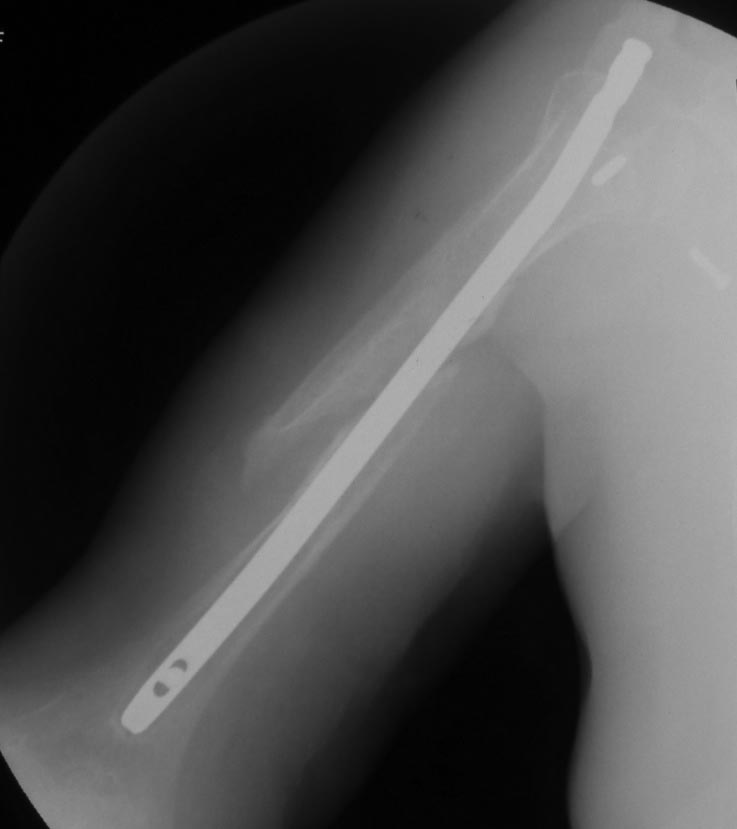

Как бы автор вопроса не убеждал себя, что в ситуации с гвоздем (его длиной, расположением относительно манжеты и бугорков и т.д.) все ясно, при таком качестве представленных рентгенограмм в единственной проекции никакой ясности быть не может.

В качестве примера - случай, который оперировал всего 2 недели назад, после похожего остеосинтеза, выполненного год назад. Пациентке 75 лет, тяжелый РА, легла для решения вопроса о ревизии тазобедренного сустава и заодно пожаловалась на то, что рука "крутиться" сама по себе, не поднимается. И болит, конечно. И посмотрите на разницу в информации на снимках головки плеча в двух противоположных проекциях. Даже комментировать ничего не нужно.